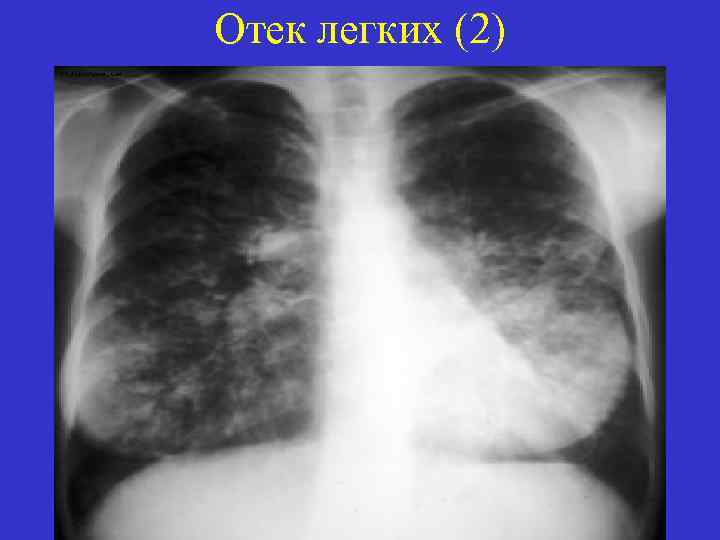

Отек легких (2)